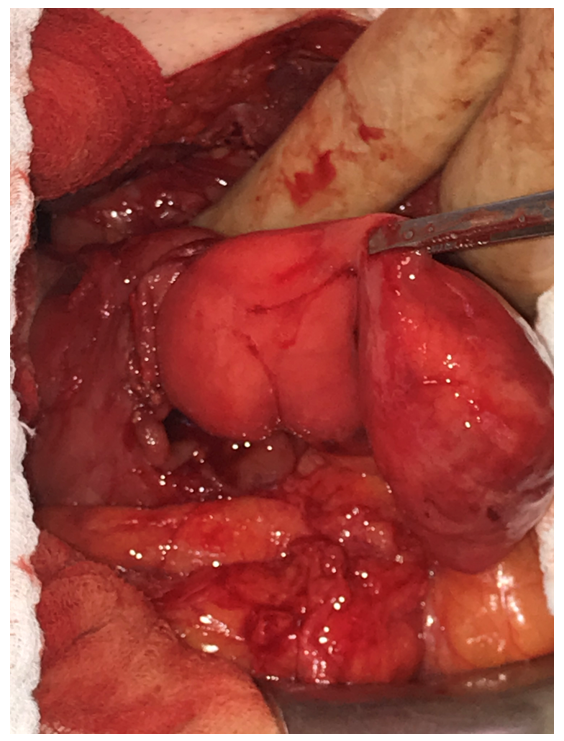

| Figure 4: Operative photo: Redo upper abdomen midline laparotomy. A longitudinal incision of the anterior aspect of the second part of the duodenum revealing a submucosal, yellowish mass originating from the posterior wall |

Due to his surgical history, laparoscopy was not found to be a safe surgical approach. We performed a redo midline, upper abdomen, laparotomy. After extensive adhesiolysis and identification of the Treitz ligament, no mass could be palpated at this level. Proceeding with mobilization of the duodenum by performing the Kocher manoeuvre, a large mass could be palpated in the descending part of the duodenum(D2). Longitudinal duodenotomy at the level of D2 revealed a pedunculated mass originating from the posterior wall of the duodenum (Figure 4-6).

Resection was performed using a powered stapler (EchelonTM flex 60 mm), positioned at the base of the stalk of this pedunculated mass after luxating it through the duodenotomy and checking for safe distance from Vater’s ampulla. After primary transverse closure of the duodenotomy, a Blake drain was placed alongside the duodenum.